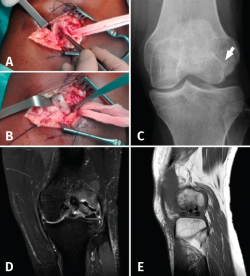

In view of the poor clinical course over follow-up and the MRI findings, surgery was indicated. Two procedures were carried out in the same surgical step. A first arthroscopic evaluation confirmed the presence of the osteochondral fracture measuring 21 mm in length, with involvement of the insertion of the tendon of the popliteus muscle, and incomplete lateral discoid meniscus rupture requiring partial meniscectomy. Partial damage to the anterior cruciate ligament (ACL) was also observed, affecting less than 50% of the ligament; no treatment was therefore required. The second procedure involved open surgery with a guided miniarthrotomy (Figure 2A) that confirmed preservation of the external lateral ligament and anterior luxation of the TP adhered to the fragment. In this procedure peripheral suturing was made entirely within the external meniscus; roughening and osteosynthesis of the fragment was performed with two 2.7 mm cannulated magnesium alloy screws measuring 20 and 24 mm in length to affix the fragment and restore the original position of the TP (Figure 2B-C).

Figure 2. A: intraoperative miniarthrotomy view (roughening of the bed and separation of the fragment indicated by the tip of the forceps); B: miniarthrotomy view after reduction and osteosynthesis of the fragment with magnesium alloy screws; C: anteroposterior radiograph of the knee showing integration of the fragment and a radiolucent image around the magnesium alloy screws (white arrow); D: control MRI images, coronal view; and E: sagittal view, showing integration of the osteochondral fragment.

After 15 months of follow-up, the patient was asymptomatic, the joint failure episodes had disappeared, and she had returned her daily activities - though she had not resumed sports activities. In the first few months the control radiographs showed a radiolucent area around the implants - these being common and non-pathological radiological signs. The control MRI scan after four months evidenced integration of the osteochondral fragment of the external femoral condyle (Figure 2D-E).